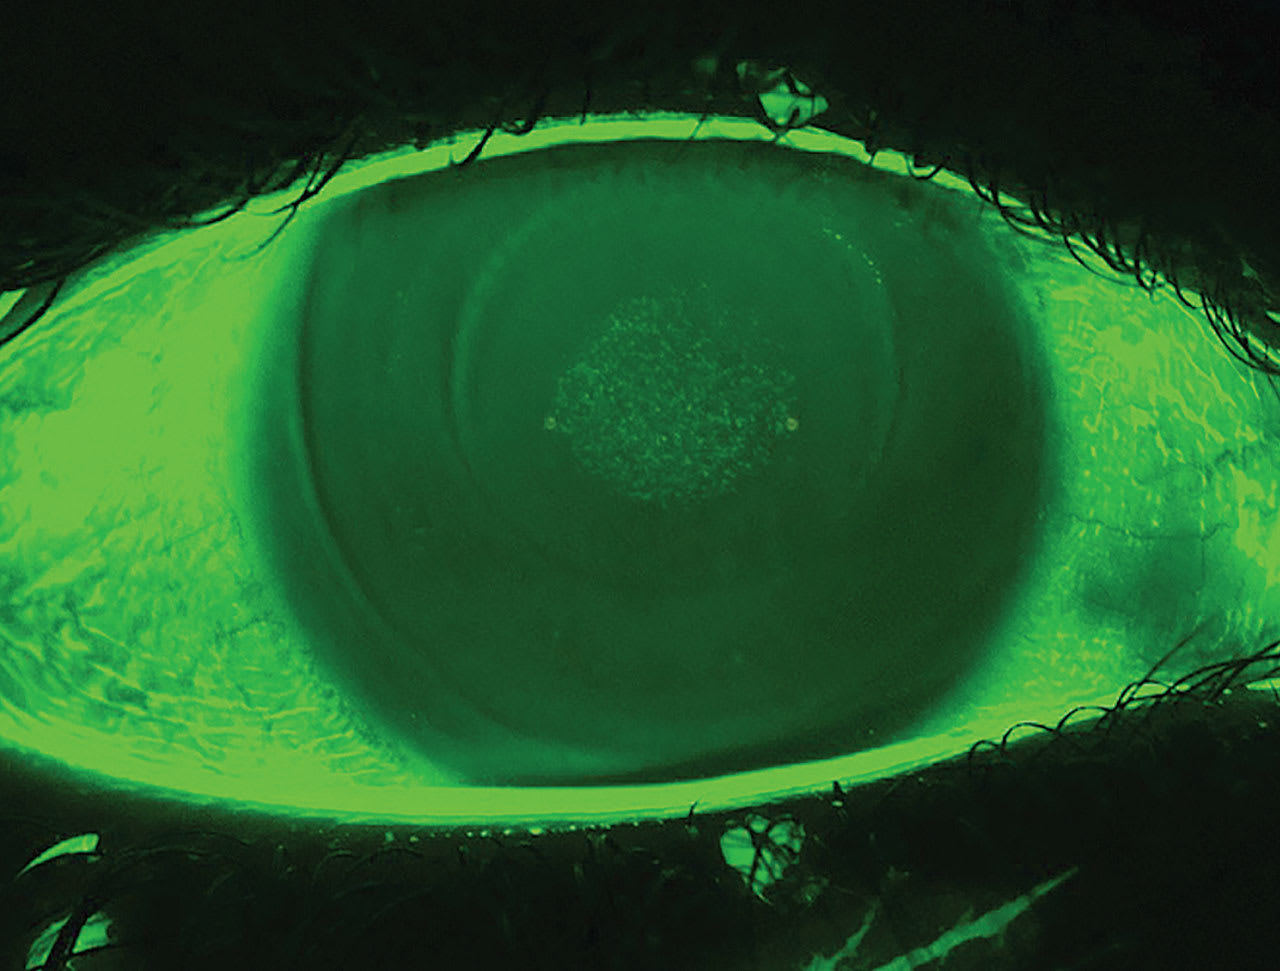

Corneal epithelial integrity is a key factor in tear film stability. Epithelial staining is one of the most commonly identified clinical signs of lens-induced corneal epithelial defects among ortho-k patients, especially in the early stages of treatment.1 Compromised corneal surface integrity induces dry eye through the following mechanisms:

Specifically, lens centration and movement should be carefully assessed to ensure uniform weight distribution of the lens, and persistent corneal staining—especially when dense and coalesced— should be addressed promptly.